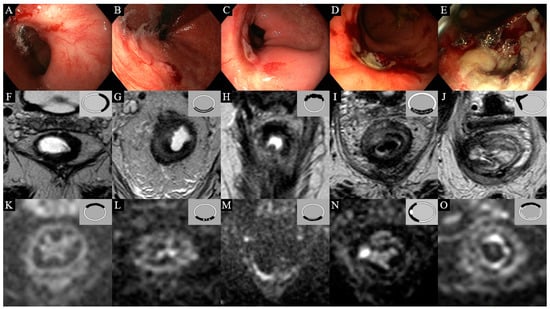

3.1. Features on Endoscopy

3.2. Features on T2W-MRI

3.3. Features on DWI